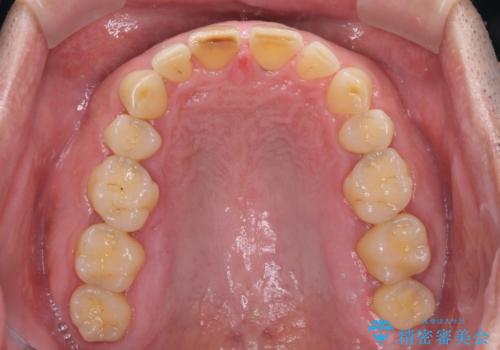

- 前歯の目立つ隙間を気にして来院された患者様です。

高校生の頃に矯正治療を行ったものの、強い咬合力により上顎が拡大され、正中に隙間ができてしまいました。

通常では歯の周囲全体を削った上でクラウンを装着することが多いのですが、咬合力が非常に強く、クラウンではセラミックが欠けてしまう可能性が考えられたため、咬合を変えることとのないラミネートベニアにて治療を行うこととしました。